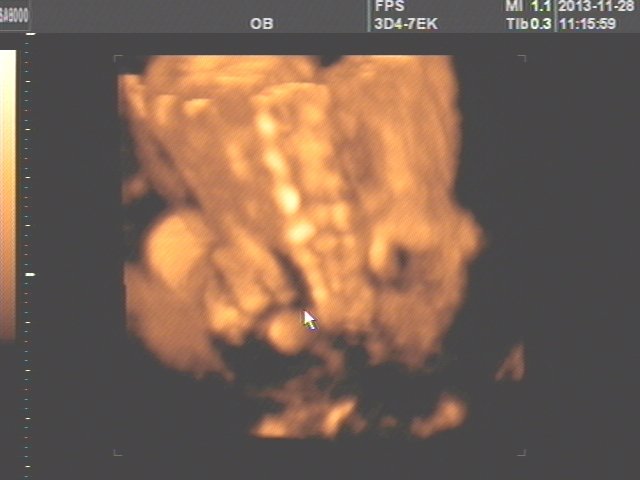

上面一张应该是脊柱,下面一张是宝宝的脸,成像的效果好差、、、不过你们家宝宝嘴唇有点厚,鼻子准头有肉,看来爸爸妈妈都是肉肉型身材劣录。下巴尖尖的,好可爱。 这样的照片你能猜到竞们吊是男是女我给射躬你写个服字!!!